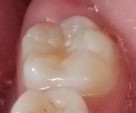

Bệnh nhân: Ng. Bá Tuấn Đ. 6 tuổi, răng 36, mã BA 6320/17

Sau sáu tháng. ICDAS: 2; Di: 21 | Sau chín tháng. ICDAS:1; Di: 19 | Sau 12 tháng. ICDAS: 1; Di: 14 |